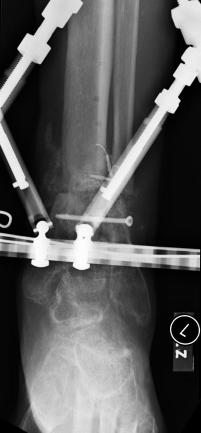

Pre-corrective surgery X-Rays of the damaged right & left legs / ankles

These x-rays were taken at Dr Armendariz’s office, just prior to performing any corrective surgery. As can be seen in these images,

there was no tibia bracing provided by Dr. Keller. Liam was released from Dr Keller’s care with instructions that full weight bearing could

be accomplished within 2 months of Keller’s last surgical procedure. The best example to examine is the second image (from the left) of the

top how. Notice how the bones that should be aligned with the tibia are in fact on the other side of the leg. The third image shows how badly

Liam’s left foot was twisted as a result of the pool placement of the external fixation. What is not obvious is that the screw at the bottom

of the plate on the right fibula missed being screwed into the plate.